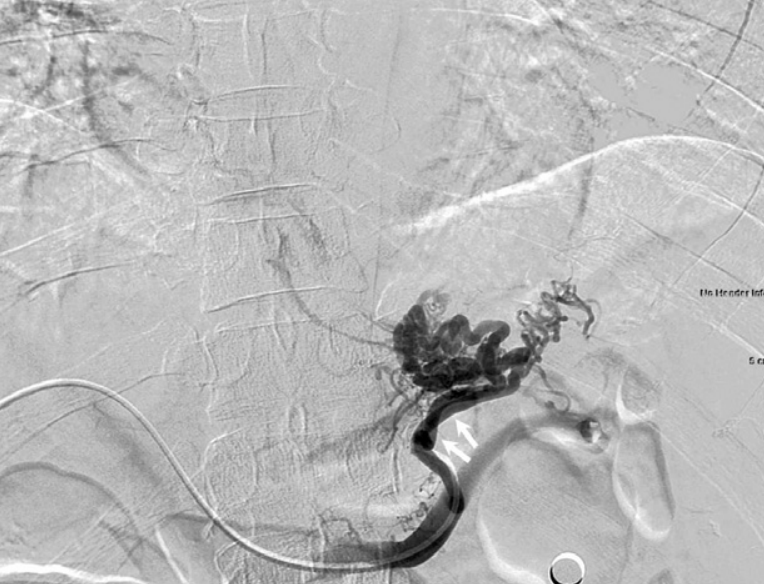

CT에서 위분문부 정맥류가 관찰되며(Fig. 1), 정맥류와 하부식도정맥류의 연결은 있었지만 gastrorenal shunt나, left inferior phrenic vein, pericardiophrenic vein 등의 유출 정맥과의 연결은 없었음.

Fig. 1

Enhanced CT scan demonstrates gastric cardiac varices (arrow).